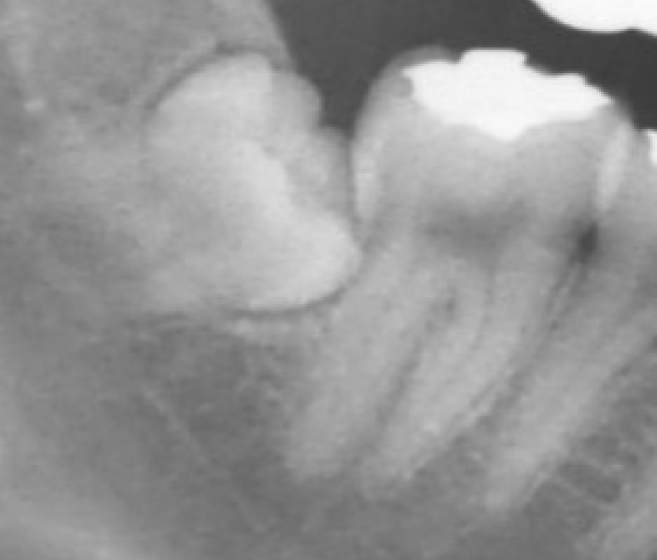

親知らずの根が下歯槽菅(神経の管)に当たっています。

親知らずの頭を切り、装置を付けて矯正で引っ張っていきます。

3週間~1ヶ月程引っ張り抜歯します。